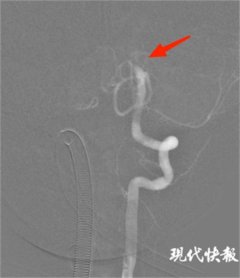

• 8岁男孩患支原体肺炎后突发脑梗,医生取出血栓块转危为安

小宝 肺炎 取栓 2023/11/29